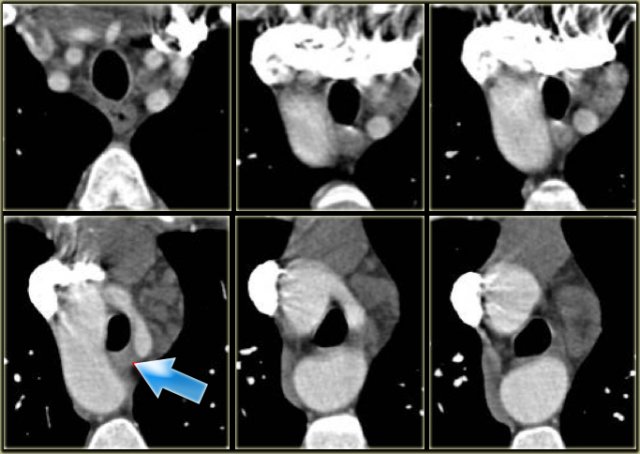

Right Arch with Aberrant left subclavian

On the left a patient with a right arch with an aberrant left subclavian (indicated by the yellow arrow).

Scroll through the images on the left.

Again you have to realize that the axial CT-images have a 'view from feet'.

There is a right arch and the left subclavian artery is the last branch of the aortic arch, indicating that this is an aberrant left subclavian.

Medially to the left subclavian artery we see the left common carotid, that originates from the right side and has an oblique course to the left.

The yellow arrow indicates the azygos vein.

The green arrow indicates the left superior intercostal vein, a normal variant, that we will discuss later.

Posterior oblique view: Right Arch with Aberrant left subclavian (yellow arrow) Posterior oblique view: Right Arch with Aberrant left subclavian (yellow arrow)

Same patient.

Posterior oblique view of volume rendered image to show the aberrant left subclavian artery.

Right Arch with Aberrant left subclavian Right Arch with Aberrant left subclavian

On the left images of a symptomatic child.

On the axial image there is a right arch with the left subclavian artery that comes off on the posterior side and runs behind the trachea and the esophagus.

The compression of the trachea is demonstrated on the volume rendered view.